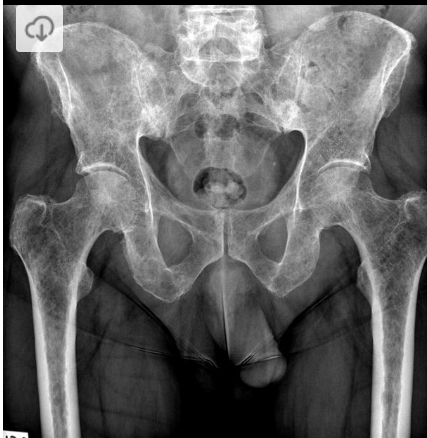

Masculino, 12 anos

Síndrome da sincondrose isquiopúbica assimétrica (Doença de Van Neck-Odelberg)

Variante da normalidade (em geral assintomático)

Crianças

Alargamento e radioluscência na sincondrose isquiopúbica, que simula neoplasias, infecção;